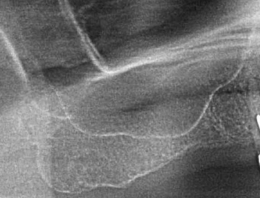

サイナスリフト症例(治療前後のCTもしくはパノラマ写真)

↓

↓